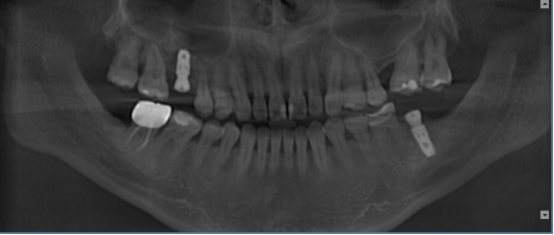

1.提供各种颌面信息及三维图像信息,精确地获得所需术前诊断信息。

2.为种植提供测量颌骨宽度、长度、密度及各种距离、角度等综合信息,以选择各种种植体尺寸及位置。

3.重要结构的定位,种植体间距离安全碰撞检测(神经管、上颌窦、病变位置等)避免手术中发生突发情况。

4.真实模拟种植体的位置,可选择任意种植型号、大小尺寸等,方便医患直观交流讨论。

5.定制手术外科导板,精确定位种植体位置及方向,提供微创及即刻种植方案